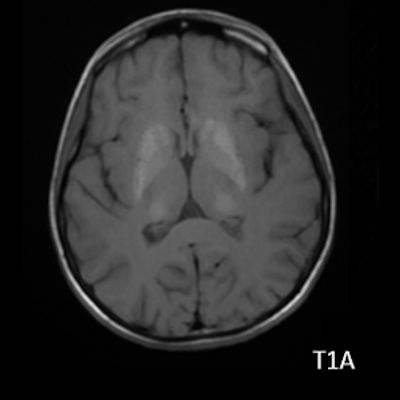

- B) Aksiyel T1A görüntülerde her iki lentiform ve kaudat nukleuslarda, talamuslarda simetrik hiperintensite (oklar) izleniyor. Bu düzeyde tariflenen sinyallerin SWI ve faz görüntülerde kalsifikasyon ile uyumlu olduğu görülmektedir (oklar). T2A görüntüde yaş ile uyumsuz serebellar atrofi ile uyumlu foliada derinleşme ve 4. ventrikül genişliğinde artış izlenmektedir (oklar).

- BT’de birden fazla lokalizasyonda multipl enfarkt benzeri odaklar ve özellikle ileri yaş hastalarda belirginleşen bazal gangliyon kalsifikasyonları izlenebilir. Lezyonlar çoğunlukla pariyeto-oksipital ve pariyeto-temporal bölgelerde yoğunlaşır ve serebral atrofi eşlik edebilir.

- Subakut dönemde kortikal laminar nekrozu temsil eden “Black toenail sign” bulgusu görülebilir.